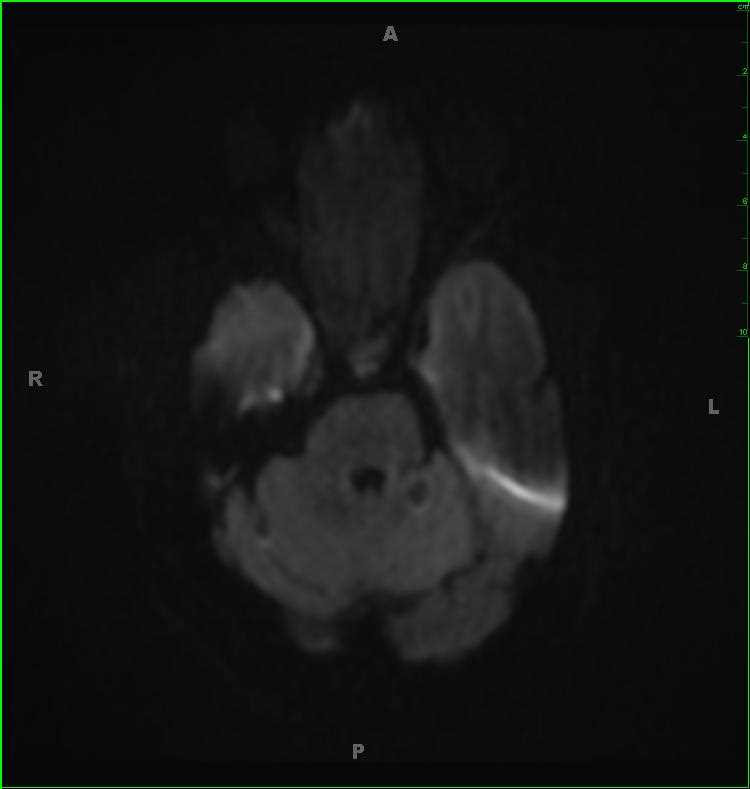

Sinonasal Undifferentiated Carcinoma (SNUC)

63-year-old female with a longstanding history of anosmia and nasal obstruction. There is a T1-hypointense, T2/FLAIR-isointense, enhancing nasal cavity mass. The lesion restricts diffusion. The mass extends into the anterior cranial fossa, including involvement of the olfactory fossa. A differential of esthesioneuroblastoma, squamous cell carcinoma, and sinonasal undifferentiated carcinoma was given. There are T1-hyperintensities in the bilateral maxillary antra and ethmoid air cells compatible with retained secretions and debris secondary to obstruction of the sinus outflow tracts. On biopsy, this mass was a sinonasal undifferentiated carcinoma or SNUC. SNUC is a rare and highly aggressive neoplasm of the paranasal sinuses. Tumors tend to be large and advanced at initial presentation. Prognosis is poor, with treatment typically entailing wide excision followed by radiation and chemotherapy.